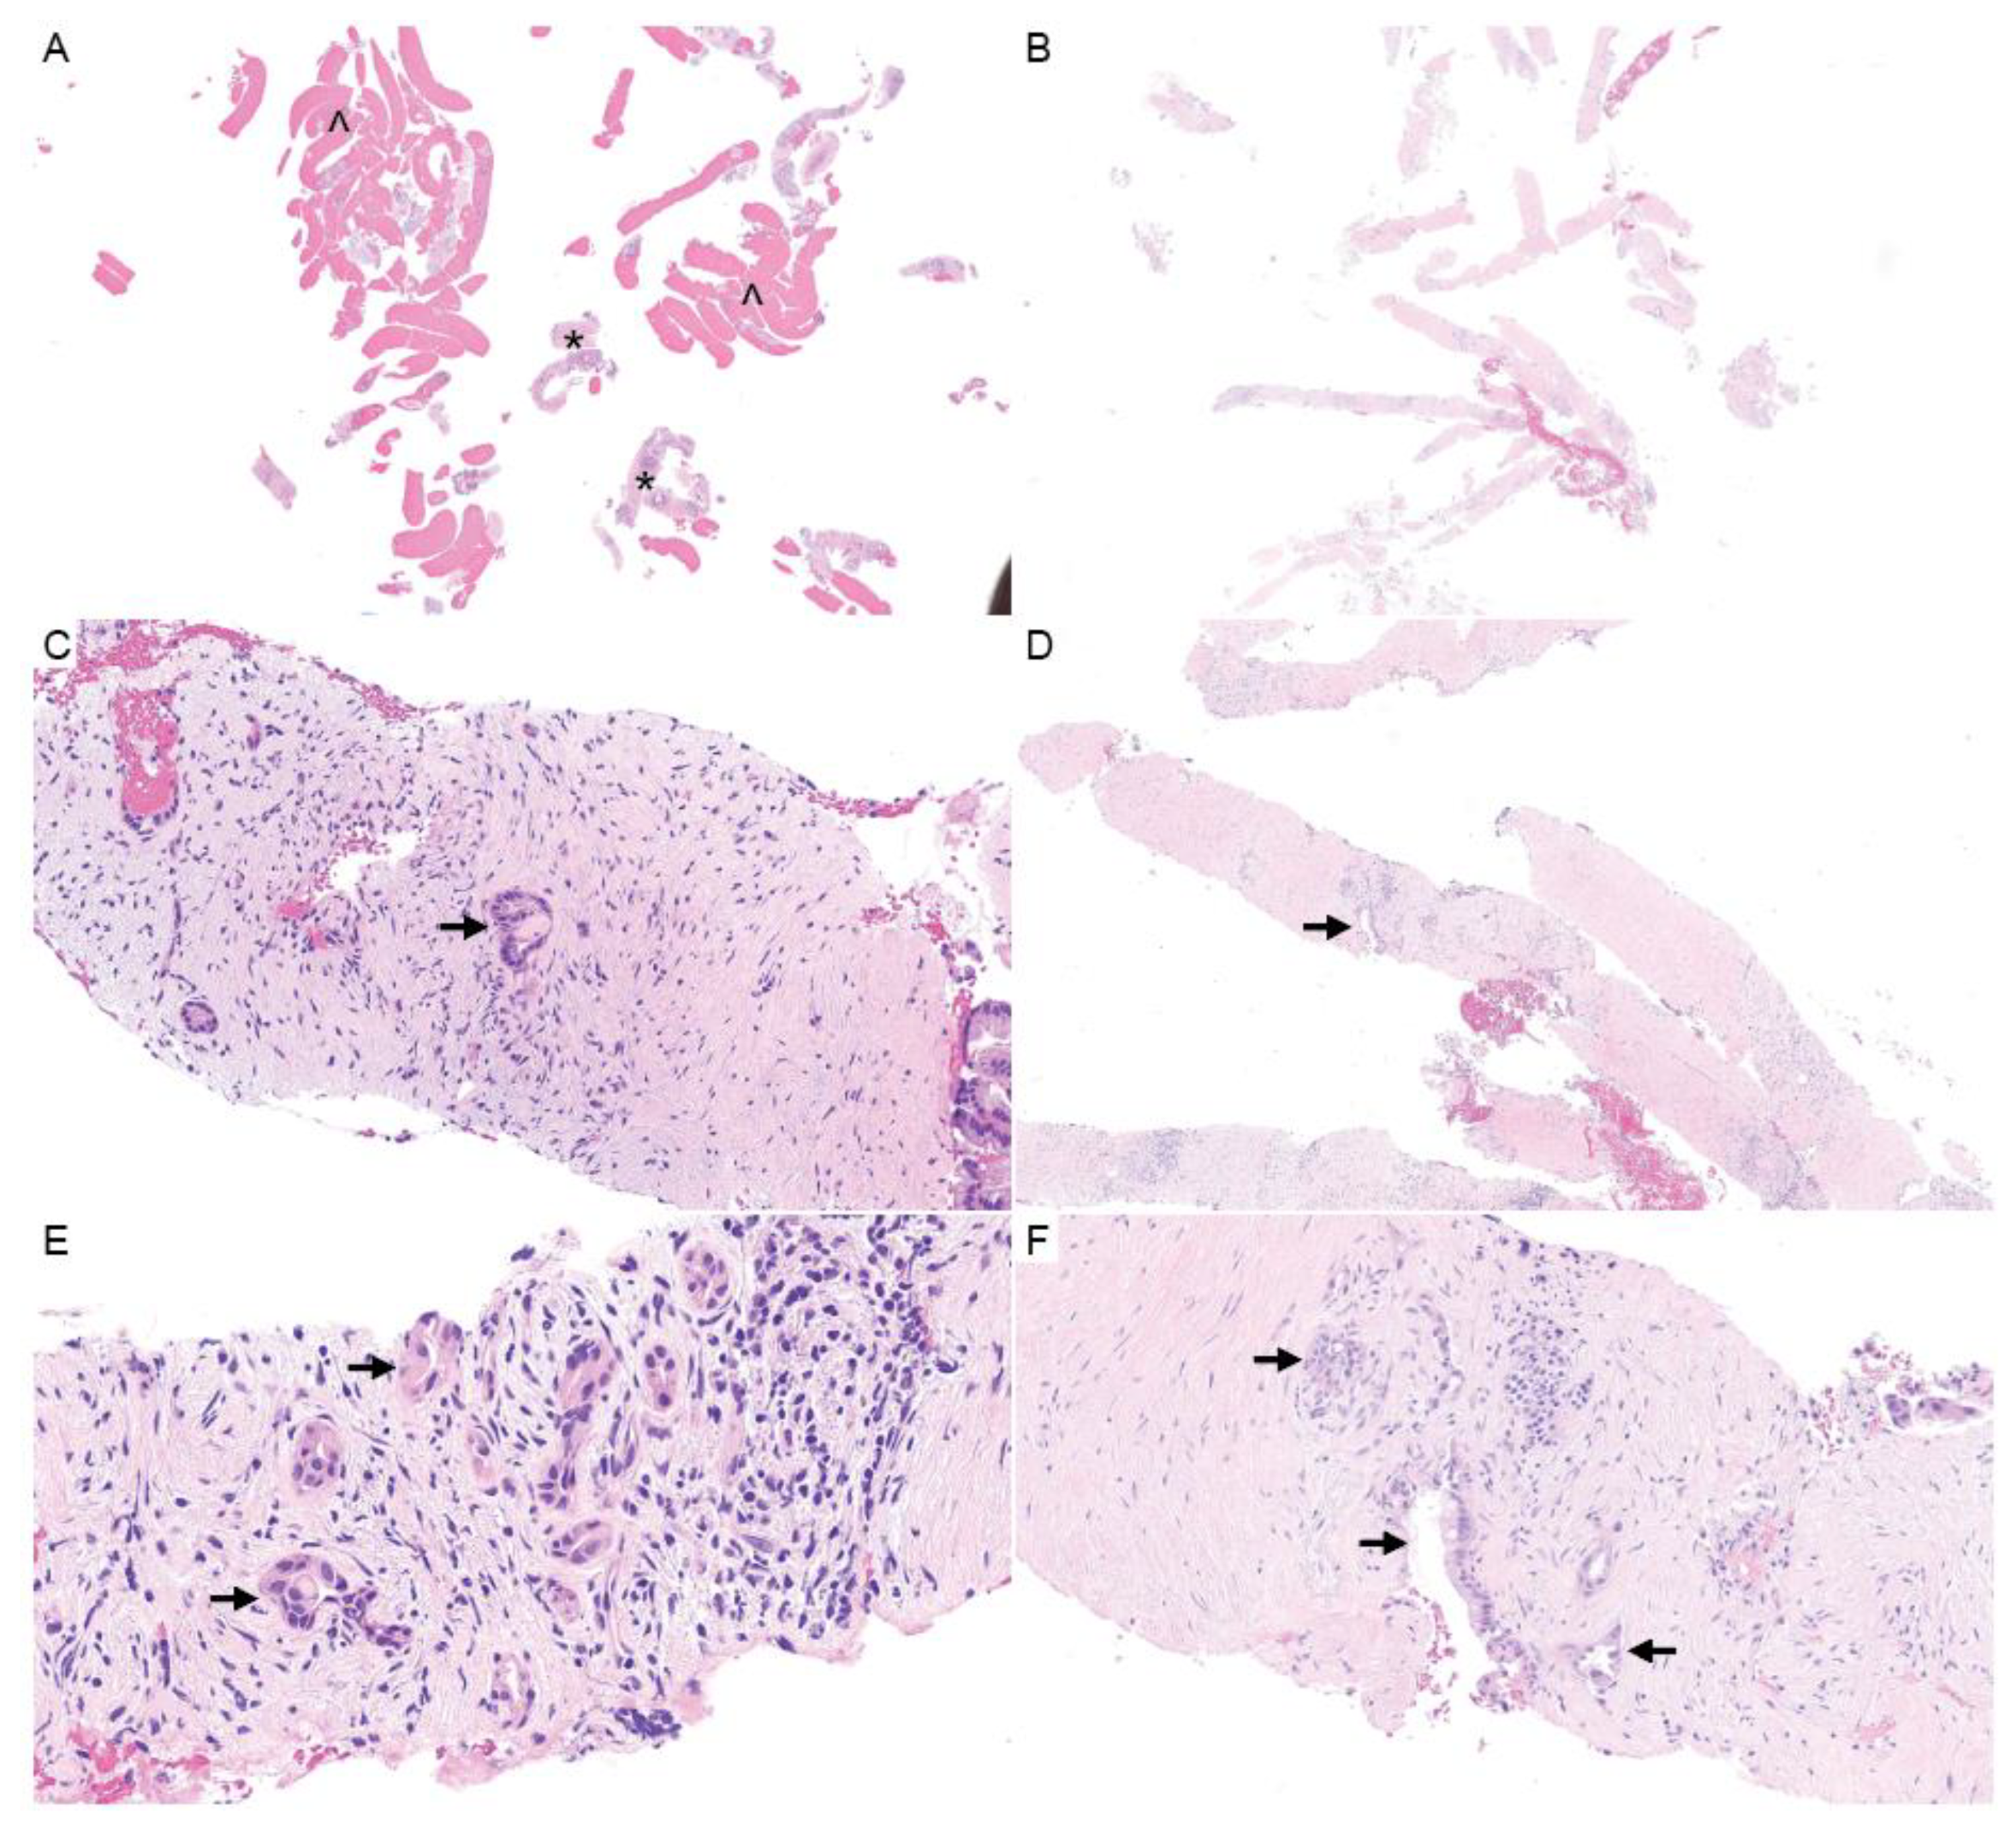

5.1.1. Sampling the TME in Small Biopsies

5.3.1. Perineural Invasion

5.3.2. Nerve–PDAC Interactions